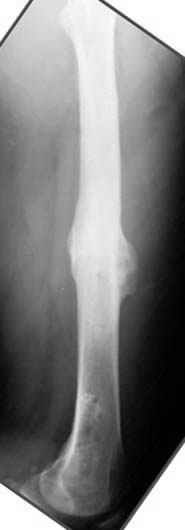

На рисунке N1 предоперационный план лечения ложного сустава шейки бедра- линия ложного сустава, угол и направление введения импланта, клиновидная остеотомия в градусах и миллиметрах, второй снимок после коррекции, расчет, на сколько удлиняется конечность и размеры импланта;

N3 рисунок окончательный снимок, после операции моя рентгенограмма должен выглядеть примерно как эта картина. На N4 снимке клин перед удалением; N5 послеоперации 3 нед.; N6 окончательная рентгенограмма.

варус при проксимальном отделе 95 градусной пластиной.

пластическая модель; и коррекция бедра аппаратом Илизарова.

Узкий к-м канал - тонкий гвоздь- усталостный перелом дистальных винтов - развитие нестабильности и как ее результат остеолиз вокруг гвоздя - деформация анатомической оси бедра. Похоже, что я понял почему аппарат, а не новый гвоздь:-)

ЕТ - Изначально костно-мозговой канал бедра был узкий, дальнейшее его рассверливание ещё больше скомпрометирует прочность бедра( латеральный кортекс дистального отломка уже истончен), приведет к дефекту наружной стенки - хотя это только мои догадки - хотелось бы знать мнение Джолдаса о выбранной тактике.